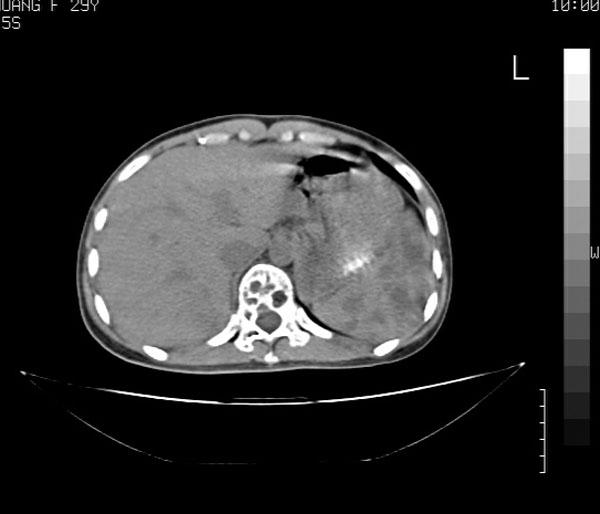

考虑多发骨髓瘤可能性大。(骨松质内弥漫性分布,边缘清晰的溶骨性破坏,无硬化。睥脏增大,其内有多个圆形底密度影。淋巴瘤不除。

脾及椎体多发占位病变.

脾脏及椎体多发占位病变。首先考虑淋巴瘤,其次骨髓瘤。建议查本周氏蛋白

2/t12压缩性骨折。脾挫裂伤(建议继续扫描或b超检查)

1:胸腰椎多发破坏伴骨折,近似穿凿样,考虑骨髓瘤,但有好多不符只出1、发病年龄小、女性,2、病变似有硬化环。2:淋巴瘤可能性大,骨及脾脏均有改变(脾脏改变似与外伤关系不大)建议密切结合临床及相关检验进一步诊断,期待结果。

椎体多发性溶骨性破坏,部分融合,椎旁无软组织肿块、椎间隙正常,t12 压缩,脾脏增大,其内示多发低密度影,首先考虑多发性骨髓瘤。病人较年轻,平素无异常,转移瘤可能性小。